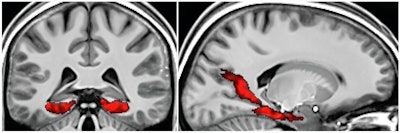

In the scene-object test, fMR images show memory activation from the posterior medial temporal lobe to the occipital cortex, incorporating both the posterior parahippocampal gyrus and retrosplenial cortex. Images courtesy of Neuron.

In the scene-object test, fMR images show memory activation from the posterior medial temporal lobe to the occipital cortex, incorporating both the posterior parahippocampal gyrus and retrosplenial cortex. Images courtesy of Neuron."Interestingly, the algorithm realized [that] big-loop recurrence has striking parallels with cutting-edge machine-learning neural network architectures that utilize external memory to solve problems of real-world relevance, typically referred to as 'question answering,' " the authors wrote.